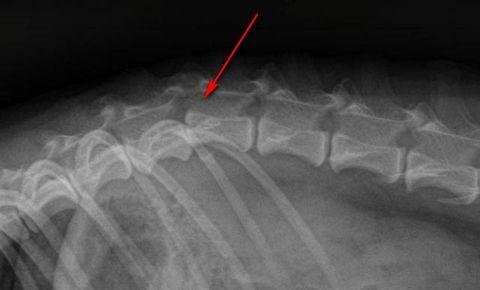

- наличие или отсутствие переломов и смещений;

- переломы;

- трещины позвонков;